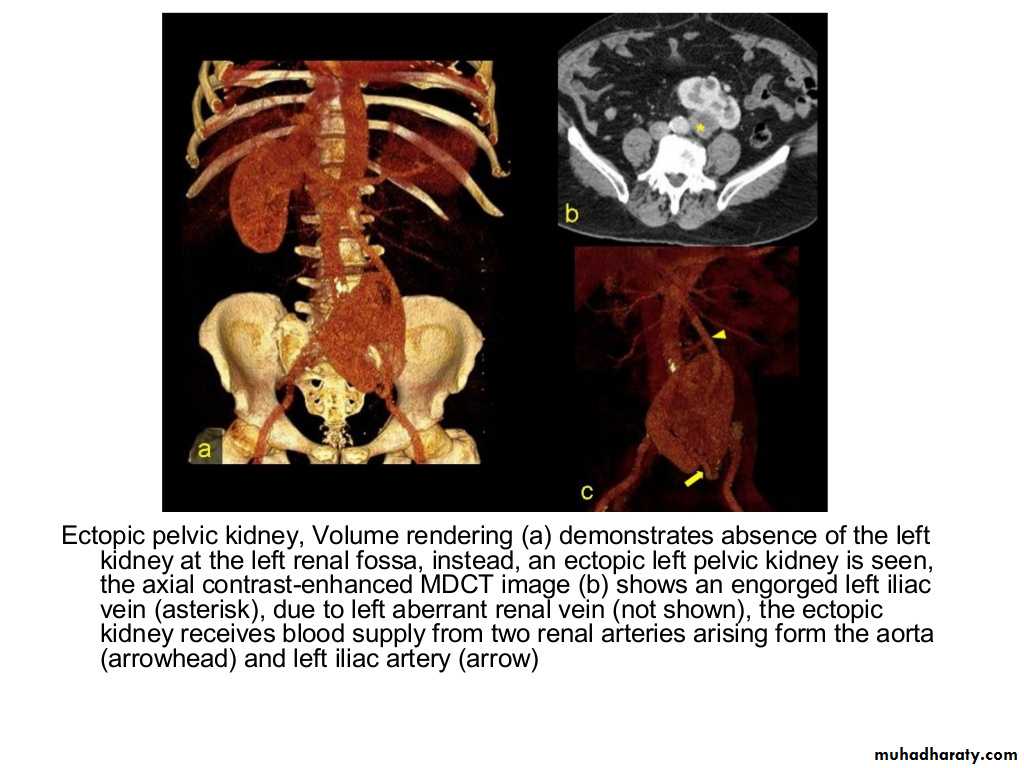

IVU shows

1. The kidneys at low position .2.Close to the spine with long axis parallel to the spine

3. Malrotation manifested by medially directed calyces.

4- The renal pelvis and ureters are anterior and lateral in position.

5- Hydronephrosis and calculi highly associated.